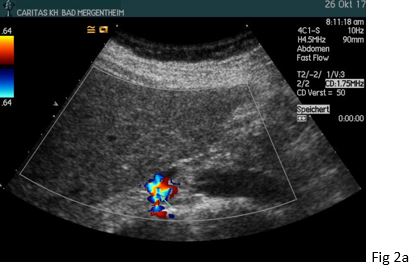

Figure 2: The retrocavally located right renal artery could be visualized posterior to the inferior vena cava (IVC) with a bruit in (a) and turbulent flow above 4 m/s in (b).